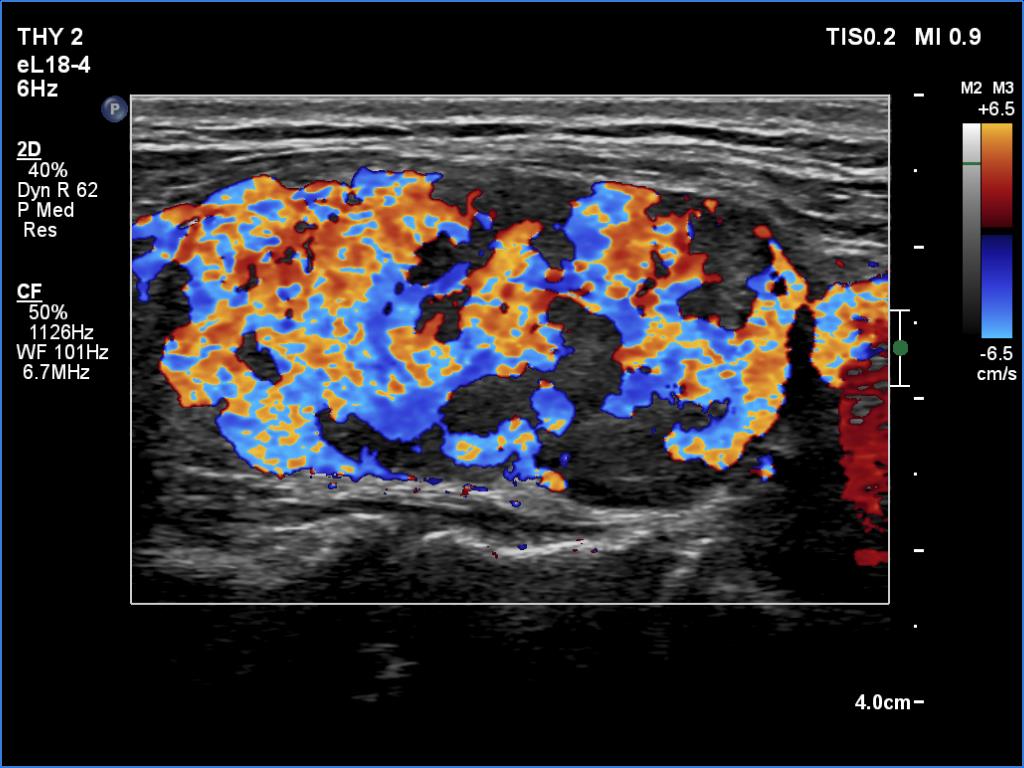

Ultrasonography. The right lobe was replaced by connective tissue. The left lobe was composed of a central hypoechoic mass which was surrounded with thin echonormal tissue. The hypoechoic part of the lobe was composed of smaller discrete lesions. The vascularity was significantly increased both on color Doppler mode and on microflow imaging.

1. A central hypoechoic mass surrounded with an echonormal tissue is one of the most common presentations of a subtotally resected thyroid.